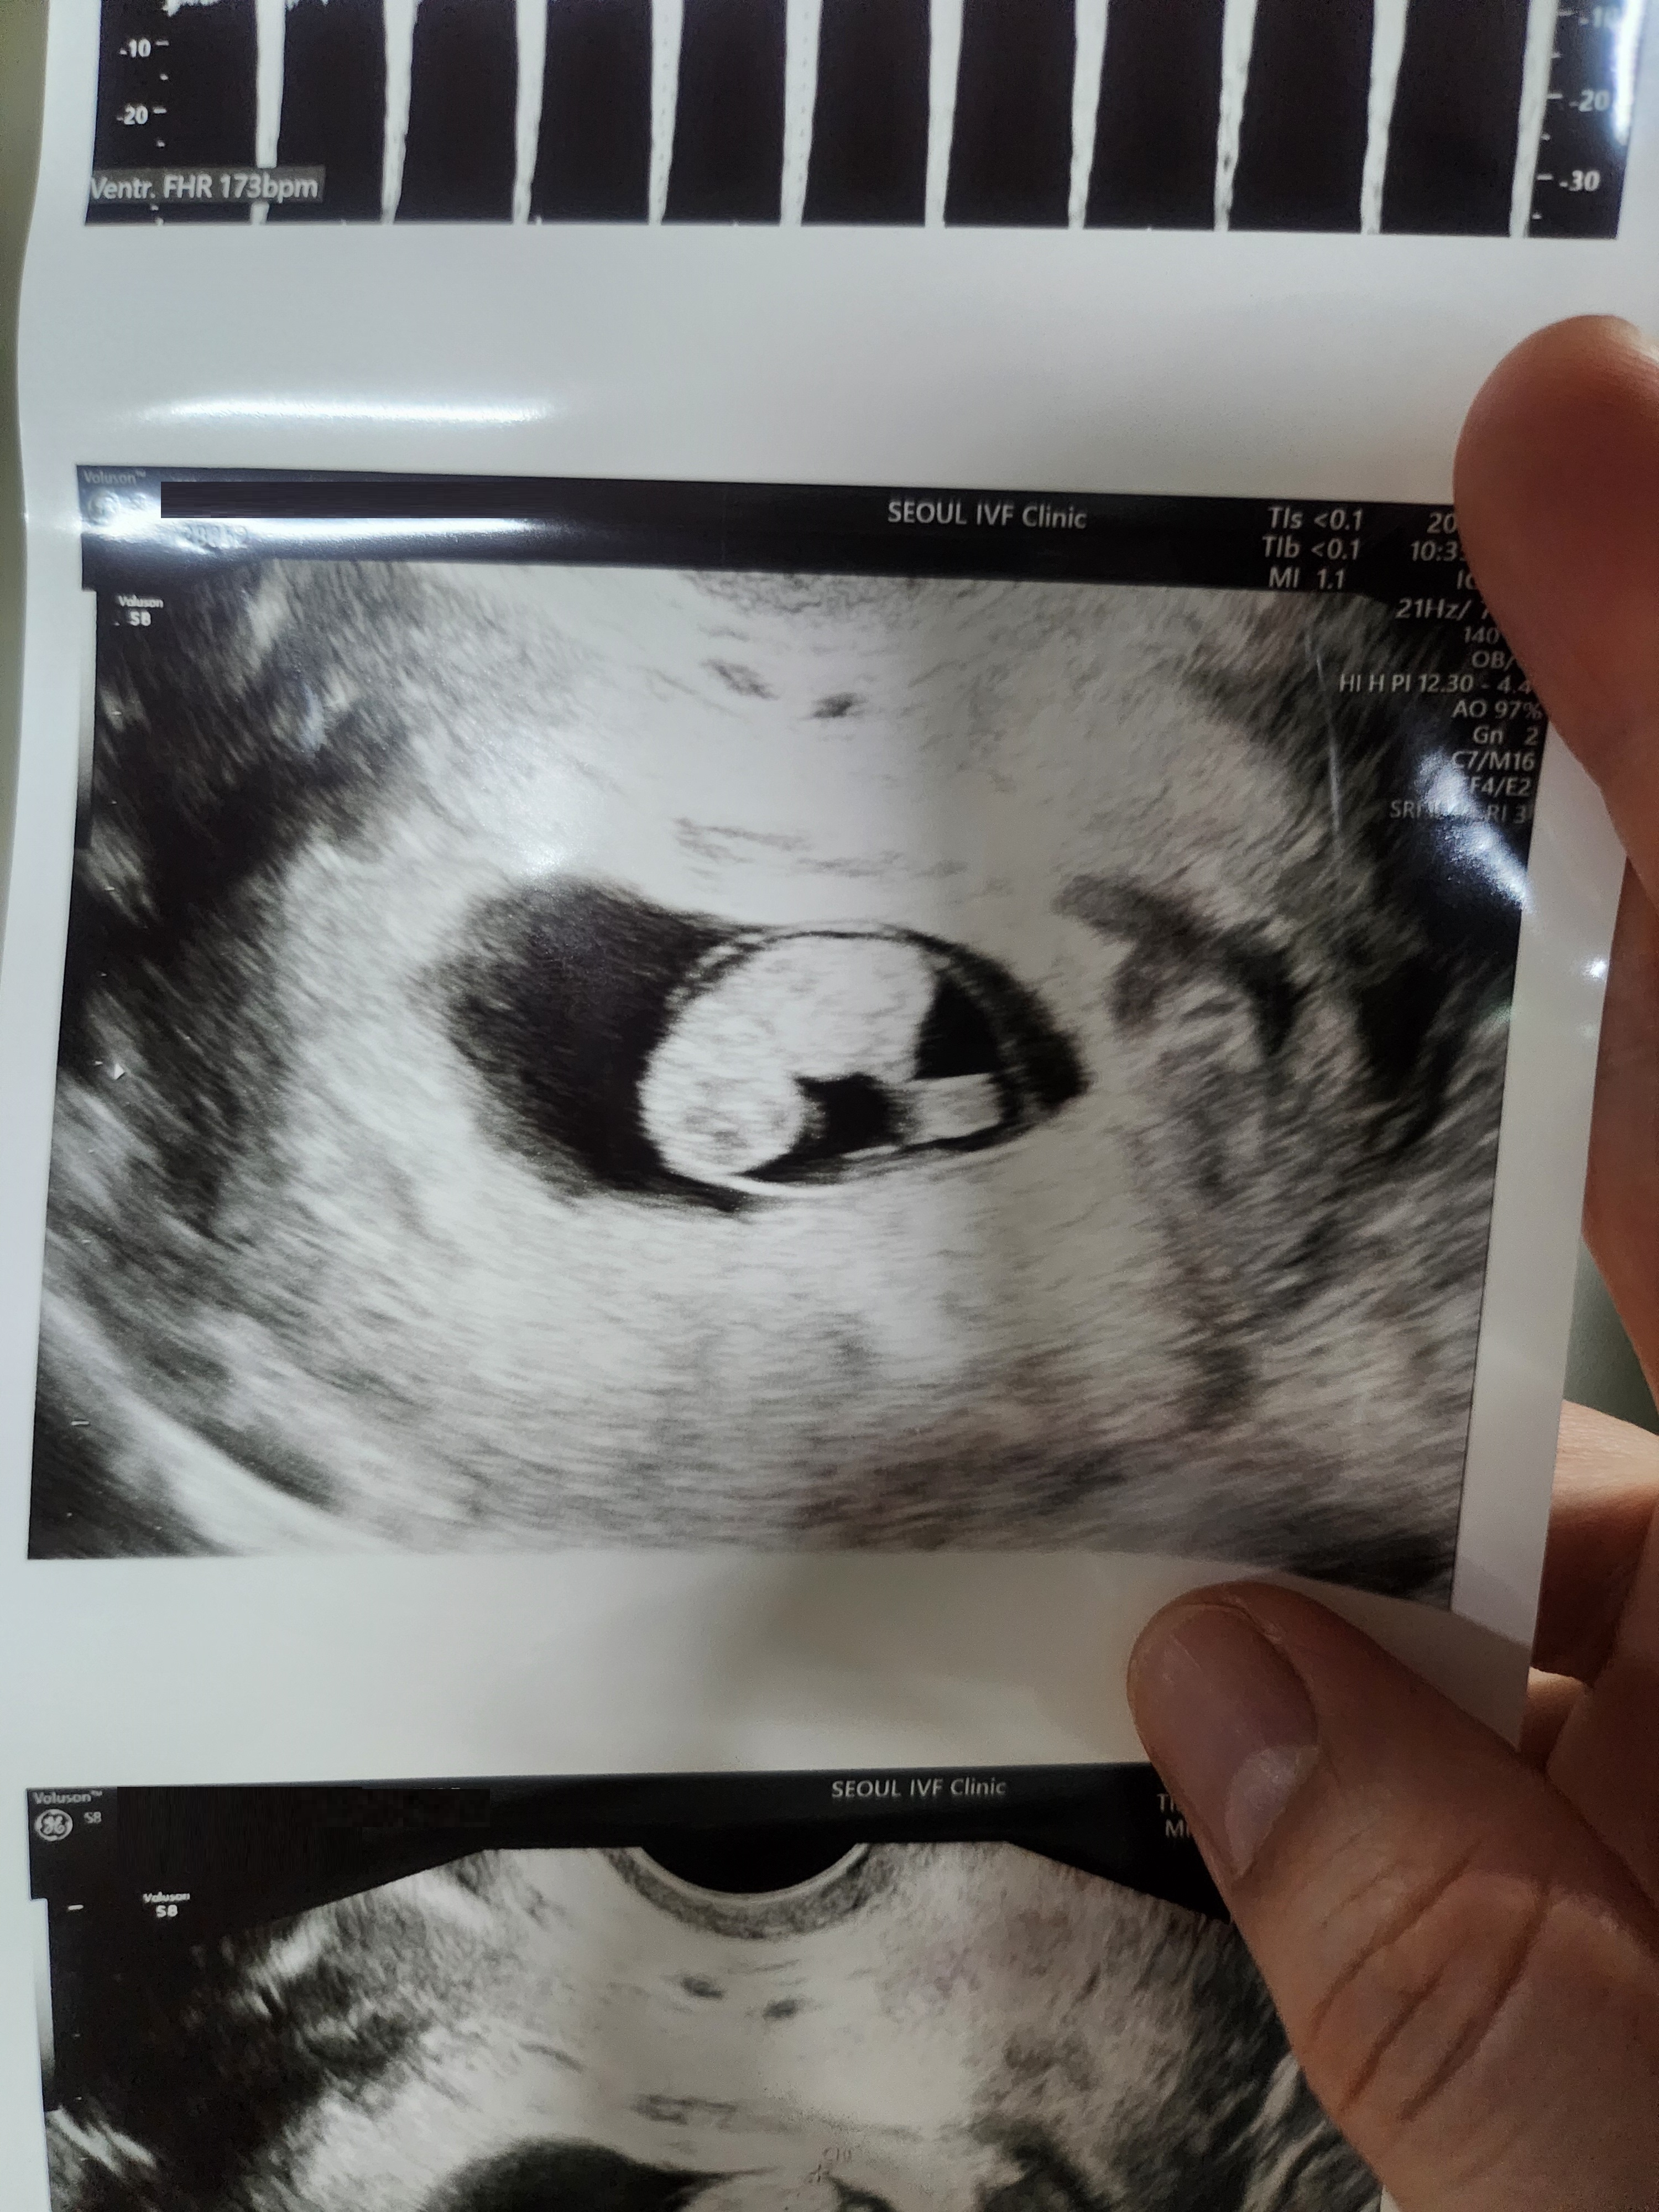

| 치료 도중 느꼈던 가장 기뻤던 순간과 절망적인 것들은 무엇인가요? 잊지 못할 경험이 있나요? | 시험관 시술 후 특별한 증상이 전혀 없어서 기대하지 않고 있었는데, 이식술 닷새 만에 임신테스터기에 두 줄이 떠올랐을 때는 믿기지 않을 정도로 가슴이 벅찼습니다. 물론 아쉬운 순간도 있었습니다. 첫 번째 시험관 임신 후 화학적 유산 소식을 들었을 때 잠시 마음이 흔들렸지만, 다시 마음을 다잡고 도전했습니다. 그리고 7주 차에 접어들어 아기의 심장 소리를 처음 들었을 때, 그때의 기쁨은 무엇과도 비교할 수 없었습니다. |